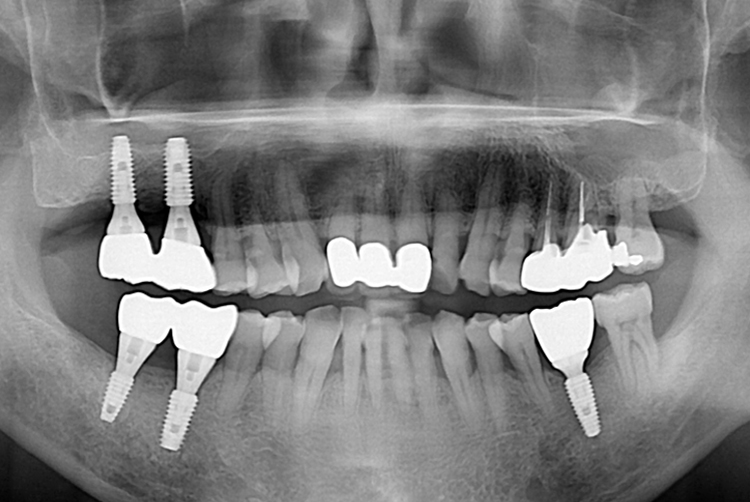

[임플란트] 임플란트

치료후 : 2018-09-28

세종치과는 많은 환자와 다양한 케이스를 바탕으로 항상 편안한 임플란트 수술을 제공하고자 노력하고,

오래동안 튼튼히 쓸 수 있는 임플란트 수술을 가장 큰 목표로 삼고 있습니다